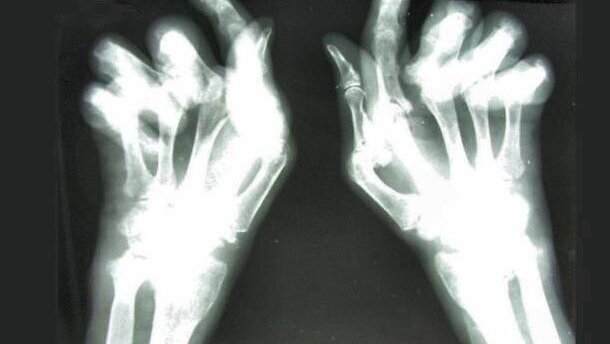

Reumatoidalne zapalenie stawów (RZS) to przewlekła zapalna choroba stawów, często prowadząca do inwalidztwa. W jej rozwoju udział biorą autoagresywne komórki układu odpornościowego, które rozpoznają własne tkanki jako obce, a następnie atakują je i niszczą. Dokładnie przyczyny tej choroby nie są znane. Podejrzewa się, że rolę odgrywają tu predyspozycje genetyczne oraz wpływ czynników środowiskowych, m.in. palenia papierosów. U osób predysponowanych genetycznie do wystąpienia RZS palenie stymuluje produkcję przeciwciał, których obecność jest cechą swoistą dla RZS, a ich pojawienie się poprzedza wystąpienie objawów choroby o kilka lat.

Ostatnie prace sugerują, że paradontoza – zapalna choroba dziąseł i innych tkanek przyzębia również może inicjować rozwój RZS i wpływać na przebieg tej choroby. W najnowszych badaniach pacjenci z RZS nie palili i nie stosowali tzw. leków modyfikujących przebieg choroby, które wpływają na czynność układu odpornościowego. Zbierano dane na temat trwania RZS, jego nasilenia, liczby zajętych stawów, a także na temat objawów paradontozy, takich jak opuchlizna dziąseł i ich krwawienie, odsłonięcie i wrażliwość szyjek zębowych, ruchomość zębów oraz przypadki utraty zęba w związku z paradontozą. Zmierzono też głębokość kieszonek między zębami a dziąsłami. Okazało się, że blisko 65% badanych pacjentów z RZS miało objawy paradontozy, a w grupie kontrolnej było ich zaledwie 28%. p

Autorzy pracy podkreślają, że ich wyniki dowodzą, że paradontoza występuje częściej i jest bardziej nasilona u pacjentów z reumatoidalnym zapaleniem stawów niż u osób zdrowych. Może ona być czynnikiem, który uruchamia mechanizmy odpowiedzialne za rozwój RZS, ale może też przyczyniać się do nasilenia choroby poprzez stymulację ogólnego stanu zapalnego w organizmie. Jednocześnie nie można wykluczyć, że samo RZS, które z czasem prowadzi do pogorszenia sprawności dłoni i osłabienia chwytu, skutkuje gorszą higieną jamy ustnej i większym ryzykiem paradontozy. Dlatego też konieczne jest prowadzenia dalszych badań, które pozwolą lepiej zrozumieć zaobserwowaną zależność.